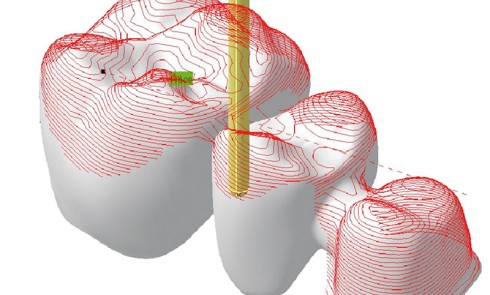

La pratique de la dentisterie numérique devient une part importante de l’activité de nombreux praticiens et laboratoires de prothèse (1)....La chaîne numérique en CFAO dentaire en prothèse conjointe

Les notions de chaîne numérique et de flux numériques sont fondamentales à la compréhension et à la maîtrise de la...Le rôle de l’assistante en prothèse fixée